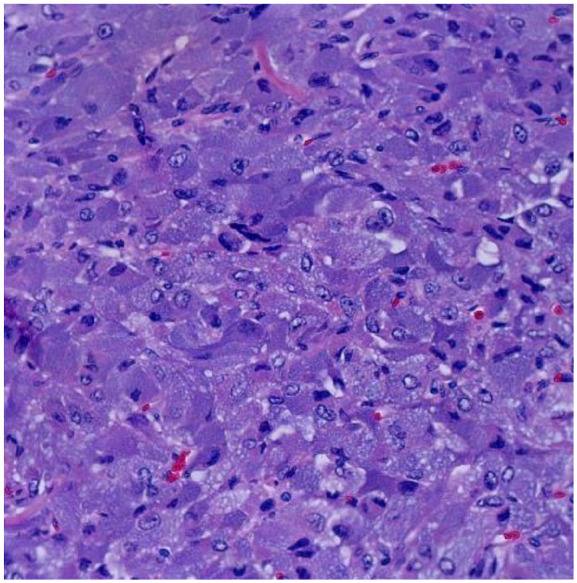

巨大嗜铬细胞瘤是一种罕见的肿瘤,通常超过7厘米。大部分是非儿茶酚胺因肿瘤坏死和结缔组织内容物而分泌。其表现可以从典型的肾上腺素能亢进症状到模糊的胃肠道不适。较大的肿瘤有较高的转移风险、死亡率和围手术期并发症。我们的病例是一位31岁女性,主诉为呕吐,伴有间歇性心悸和血压升高,随后影像学显示右侧肾上腺肿块8.7 cm。完全切除肿物显示一个10 × 7 × 3.9 cm的肿物,占据整个肾上腺髓质,符合巨大嗜铬细胞瘤。本病例为支持微创方法和个体化治疗巨嗜铬细胞瘤提供了证据。此外,它强调了在症状模糊的情况下高度临床怀疑的重要性。

Giant pheochromocytomas are rare tumors, typically exceeding 7 cm in size. Most are noncatecholamine secreting due to tumor necrosis and connective tissue content. Their presentation can range from classic hyperadrenergic symptoms to vague gastrointestinal complaints. Larger tumors are associated with higher risks of metastasis, mortality, and perioperative complications. Our case presents a 31-year-old female who presented with the chief complaint of vomiting, associated with intermittent palpitations and elevated blood pressure, with subsequent imaging revealing an 8.7 cm right adrenal mass. Complete resection of the mass showed a 10 × 7 × 3.9 cm mass that occupied the entire adrenal medulla, consistent with a giant pheochromocytoma. This case contributes to the evidence supporting a minimally invasive approach as well as individualized management of giant pheochromocytomas. Furthermore, it emphasizes the importance of a high clinical suspicion in the context of vague symptoms.